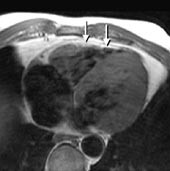

T1-vektede MR-bilder viser det normale perikard som en mørk stripe mellom to lyse vev, det epikardiale fettvev og det perikardiale fettvev (fig 8, 9). Fortykkelse av perikard ( ≥ 4 mm) kan av og til sees ved akutt perikarditt, men er mer vanlig ved kronisk perikarditt. MR er en sensitiv metode til å påvise konstriktiv perikarditt (20). I tillegg til perikardfortykkelsen, sees dilatasjon av høyre atrium, v. cava inferior og levervenene og normalt stor eller liten høyre ventrikkel. MR er imidlertid en dårlig metode til å påvise forkalkninger i perikard. Perikardvæske har et varierende utseende ved MR avhengig av innhold av protein og andre makromolekyler. Stormolekylære stoffer forkorter væskens T1 og forårsaker økt signalstyrke på T1-vektede bilder. Eksudatet i perikard ved den sterkt inflammatoriske uremiske perikarditt gir således et moderat kraftig signal på T1-vektede bilder, mens det perikardiale transsudat som sees ved f.eks. hjertesvikt, har nesten manglende signal på T1-vektede bilder (fig 7). Hemoperikardium har et karakteristisk utseende med en intens signalstyrke på T1-vektede bilder.

MR er generelt den beste teknikken til påvisning av tumorer i eller omkring hjertet (fig 9). Ingen annen metode kan som MR fremstille en tumors utbredelse og ev. infiltrasjon i hjertet og de store kar. God bildekvalitet forutsetter imidlertid en jevn hjerterytme. Spesielt små intraluminale tumorer (f.eks. myksomer) kan være vanskelige å påvise dersom bildekvaliteten reduseres av ujevn rytme. Da kan ekkokardiografi være et bedre alternativ. Enkelte ekspansive prosesser kan ved MR ha en karakteristisk signalstyrke, f.eks. lipomer og hematomer. Man kan som regel skille mellom cystiske og solide tumorer, men de fleste solide tumorer har ved MR et uspesifikt utseende.